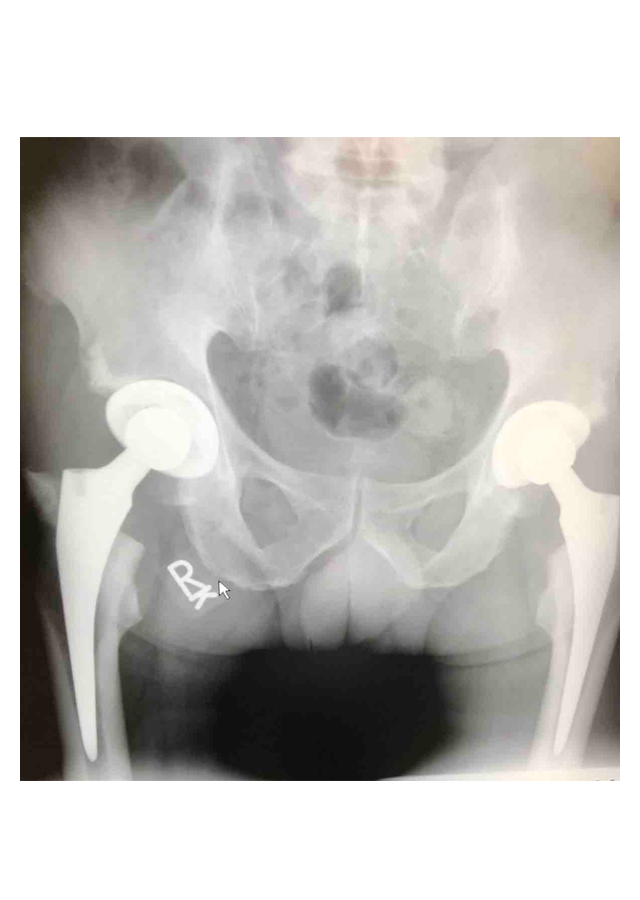

Csípő és térd ízületi betegségek protetizálása

Degeneratívtól, posttraumáson át veleszületett deformitásokig, revíziók, egyszerű és bonyolult helyzetek megoldása.